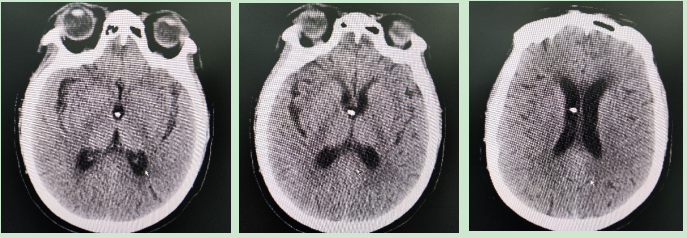

手术中,牛志强副主任医师凭借精湛的显微外科技术和丰富的解剖经验,精准地将导管尖端置入预定脑室位置,并将泵体稳妥埋置于头皮下。整个手术过程顺利,术后患者生命体征平稳。术后复查头颅CT示Ommaya泵置入位置良好。